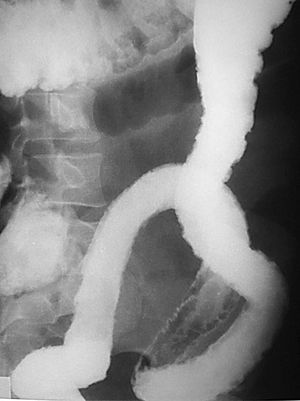

La EC se define como un proceso transmural inflamatorio crónico de etiología desconocida. De carácter recurrente, segmentario y granulomatoso, tiende a provocar complicaciones tales como abscesos y trayectos fistulosos. Se localiza en cualquier segmento del tracto digestivo, desde la boca al ano, aunque asienta de forma preferente en el íleon terminal, en íleon proximal y colon ascendente (fig. 1). Se acepta que en un 55% de los casos hay afectación del íleon terminal y del colon, en un 30% de los casos sólo de intestino delgado y que la afectación exclusiva del colon acaece en un 15%9.

Fig. 1.--Enfermedad de Crohn, afectación segmentaria del tracto digestivo con localización duodenal (A) e ileal (B) en el mismo paciente.